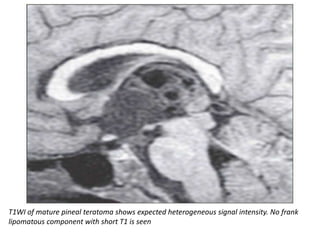

T1WI of mature pineal teratoma shows expected heterogeneous signal intensity. No frank

lipomatous component with short T1 is seen

T1WI of maturepineal teratoma shows expected heterogeneous signal intensity. No frank lipomatous component with short T1 is seen